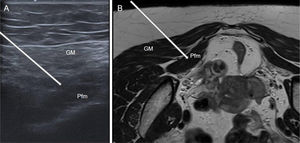

Ultrasound technique. The transducer is placed transversely over the gluteal region, with the greater trochanter positioned on the lateral side of the image and the ischial spine on the medial side. The piriformis muscle is seen underneath the gluteus maximus, extending from the sacrum to the greater trochanter, lying superficial to the ilium. If there is any uncertainty, the patient can be asked to bend the knee and perform internal and external rotation of the hip to see how the piriformis muscle moves. The sciatic nerve is identified, typically lying deep and medial to the piriformis muscle.18 (Fig. 3)

Figure 3.Theoretical course of BT infiltration in the piriformis muscle. (A) Ultrasound image, and (B) the corresponding MRI, with the course indicated by a white arrow. With the patient in the prone position, access would be from lateral to medial, traversing the gluteus maximus (GM) to reach the piriformis (Pfm).